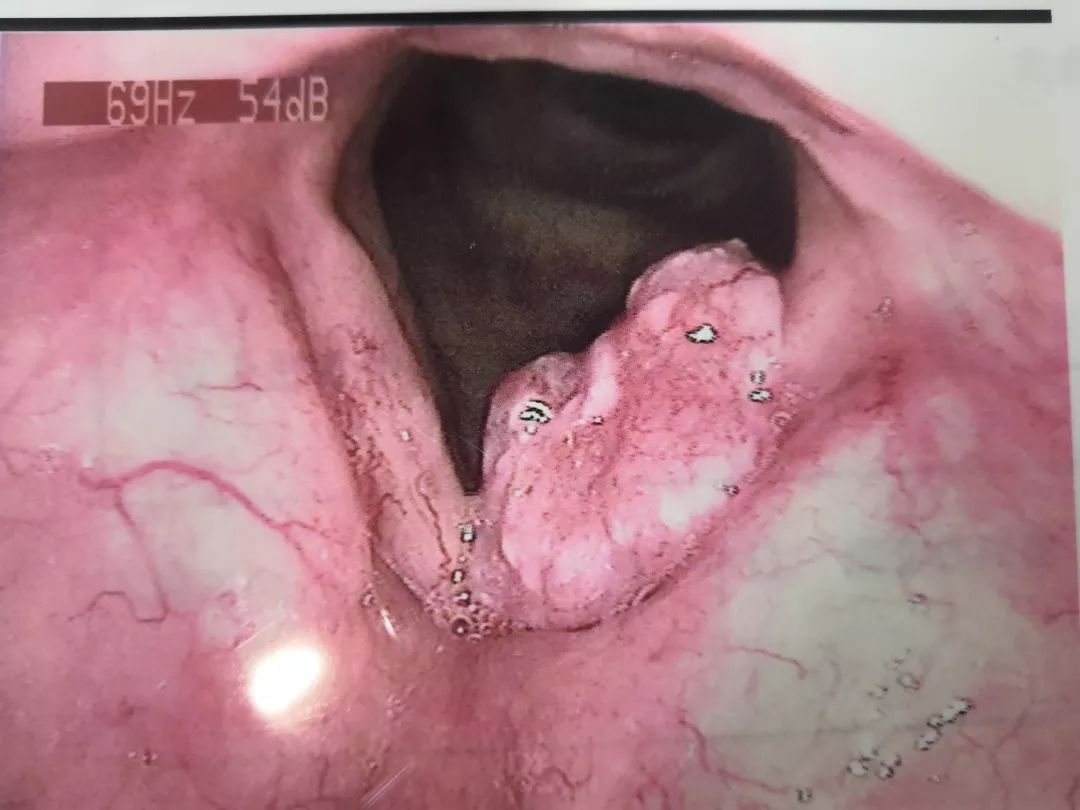

咽喉癌的早期症状图 好医师网 好医生在线 24小时免费咨询 帮您免费快速

咽喉炎图片和正常图片 自己排除喉癌的方法 帮助信息 动天数据